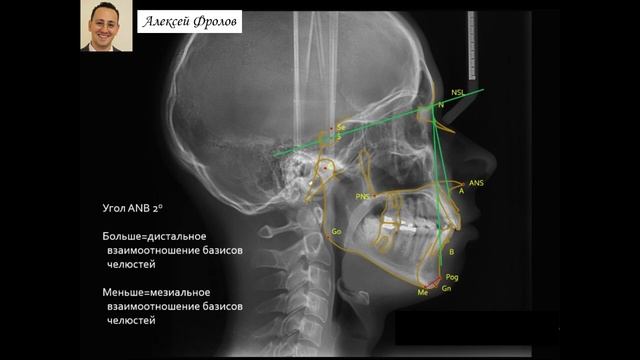

Телерентгенография. Антропометрия. Цефалометрия. (Фролов А. О.)

Для чего нужен цефалометрический анализ

Цефалометрия

Цефалометрия это

3д цефалометрия

3d цефалометрия